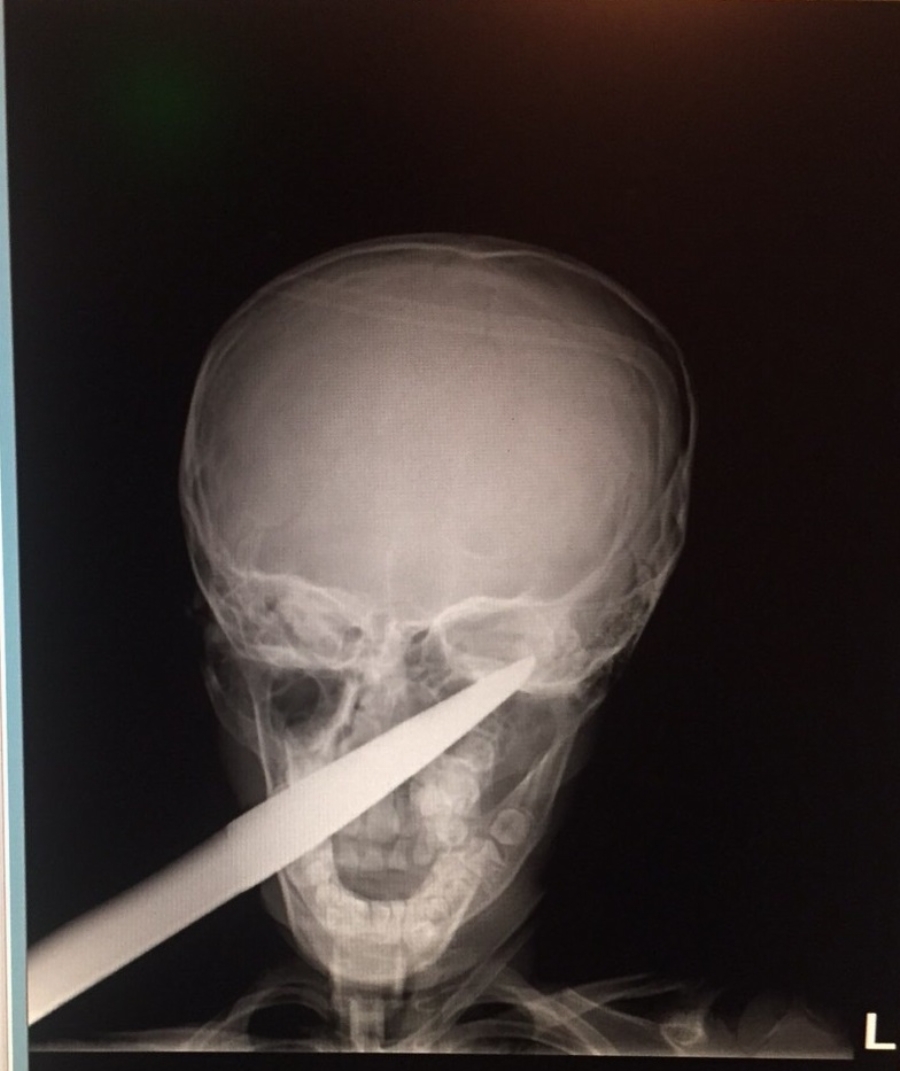

Дете оцеля по чудо след като 70 сантиметрова ножица се заби в главата му

Дете оцеля по знамение откакто 70 сантиметрова ножица се заби в главата му! Момченцето, което е седем годишно, си играело в градината и напълно несъзнателно паднало върху градинска ножица. Тя се забила в главата му. Инструментът, също така бил ръждясъл. Острието е минало през бузата на детето и достигнало до окото, преминавайки през цялата глава . " Още няколко милиметра и изходът щеше да е съдбовен " споделят лекарите от Спешното поделение на УМБАЛ Бургас. Специален екип от медици е призован незабавно, с цел да вземе най-правилното решение по случая. Спешната интервенция е осъществена, откакто на детето са направени съответните проучвания и образна диагностика.

След бързата лекарска интервенция, дребният пациент е прокиснал няколко дни в болничното заведение и към този момент е в дома си. " В цялата си над 30-годишна процедура не съм виждал сходна контузия . Оприличавам я на пострадване от военно време, каквито пострадвания в днешни дни са необичайност. Острието на ножицата наподобява на копие, на щик. В хода на интервенцията то е извадено доста постепенно, кървенето е овладяно, наложи се и кръвопреливане ", споделя доктор Даниел Петков, който е направил интервенцията.

Уникалният случай ще бъде обект на разискване на медицински конгрес, а градинската ножица, чиято дължина е 70 сантиметра, ще бъде непокътната в отделението по УНГ в бургаската болница.